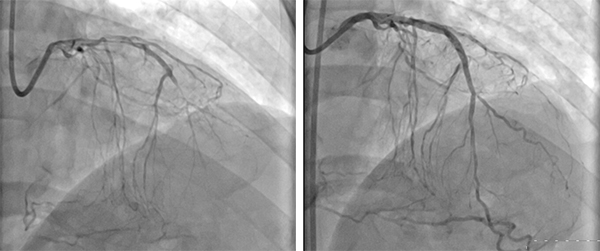

因5年多来有劳力性胸闷、气促,而前两个月加重得很明显,44岁的凌先生于2016年2月14日来我院就诊,入院后,心胸外科医生为他进一步完善检查,发...